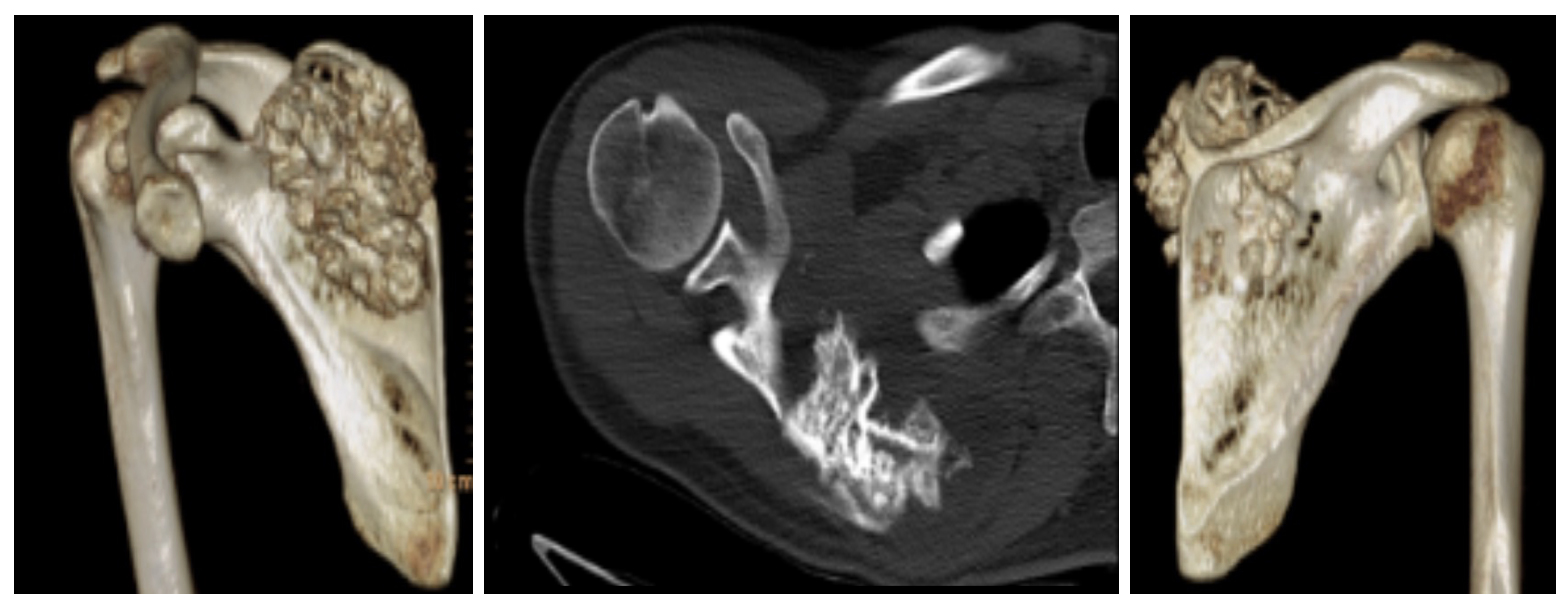

Ameliyat Öncesi: Tomografide skapulada harabiyet ve kıkırdak doku görünmekte.